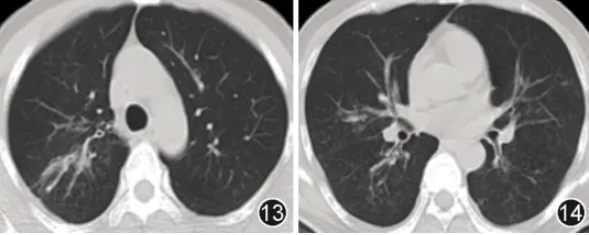

患者男,46岁,主因“咳嗽、咳痰伴发热27 d”于2025年1月27日入院。患者27 d前无明显诱因出现咳嗽、咳少量白黏痰伴发热,体温最高38.6 ℃。当地医院查血甲流IgM(+),胸部CT示双肺斑片影(图1,2),给予口服奥司他韦抗甲流、头孢菌素联合左氧氟沙星抗细菌治疗10 d后,复查胸部CT示双肺多发实变影伴空洞形成(图3,4),经验性加用伏立康唑抗真菌治疗1周后复查胸部CT示病变仍进展(图5,6)。既往史:2型糖尿病8年,口服二甲双胍、阿卡波糖、皮下注射甘精胰岛素治疗,未规律监测血糖;高血压1年,血压最高达170/100 mmHg(1 mmHg=0.133 kPa),未治疗及监测血压。无烟酒嗜好,否认过敏史,家族史无特殊。

图1,2 2025年1月4日胸部CT示双肺散在斑片影

图3,4 2025年1月14日(经抗甲流+抗细菌治疗10 d后)胸部CT示双肺多发实变影伴空洞形成